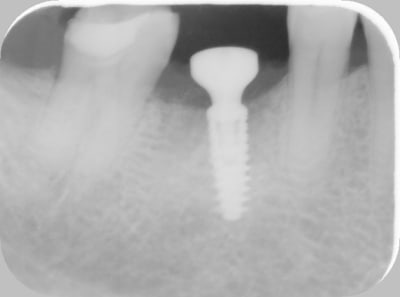

Pas de pertes osseuses, plutôt l'inverse.

Bon c'est sur, c'est un cas favorable, mais plutôt édifiant.

En tout cas j'ai une repousse osseuse sur quasi toutes mes réouvertures (après j'en ai pas encore fait 500 non plus...)

Radio jour de la pose.

Radio à j + 2 mois.

Radio avec prothèse très ankylos like. (désolé pour la qualité de cette dernière, le logiciel du pano merde...)

C'est quoi le diamêtre de l'implant ?

Semble un peu petit, non ?

Si mes souvenirs sont bons, le diamètre de l'implant c'est 4,5. Le pilier c'est 6,5.

Je n'aime pas les implants trop gros, partant du principe que plus l'implant est gros, moins il y a d'os autour (je lance le débat).

Étant donné qu'il est entièrement dans l'os, le risque de fracture du col de l'implant me parait nul (je vois pas quel autre risque il y a a mettre un implant de petit diamètre), et de toute façon le diamètre du col du pilier est le même quelque soit le diamètre de l'implant.

J'ai choisi ce système en autre car il permet de mettre une grosse dent sur un petit implant et vice et versa.

4.5 mm c'est quand même le minimum pour une molaire.

Je suis d'accord, mais sans info sur la crête de ton cas, peut-être que 5.0 mm aurait été possible, sans avoir un déficit osseux.

> Étant donné qu'il est entièrement dans l'os, le risque de fracture du col de l'implant me parait nul

L'os est élastique, et si trop de contraine, va se cratérisé, et tu n'auras pas d'os au niveau du col...

Ton implant est en fonction depuis combien de temps ?

Le succès, c'est à 3-5-10 ans, pas 3-5-10 mois.

Mis en fonction tout récemment, c'était juste une jolie radio pour donner le change à ceux qui viennent dire que les implants tekka cratérisent dès la vis de cicatrisation et qu'ils ont 30% d'échec. Parfois c'est pas l'implant qui est en cause.

TA6V. Je sais plus si ça correspond au grade 4 ou 5.